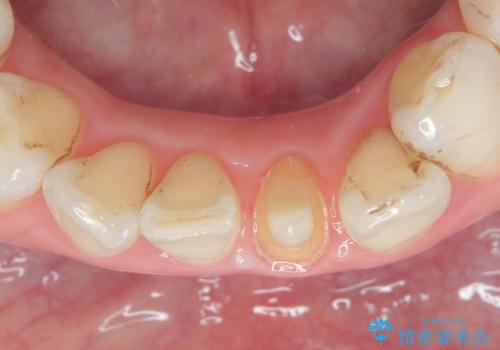

- 下顎前歯が茶色いのが気になるのでセラミックで治療したいといらっしゃった方の症例です。

再根管治療後、オールセラミッククラウン(スペシャル)による補綴を行いました。

- オールセラミッククラウン…¥100,000、仮歯…¥10,000、ファイバーコア…¥20,000、精密根管治療費別途費用は治療当時の料金となります